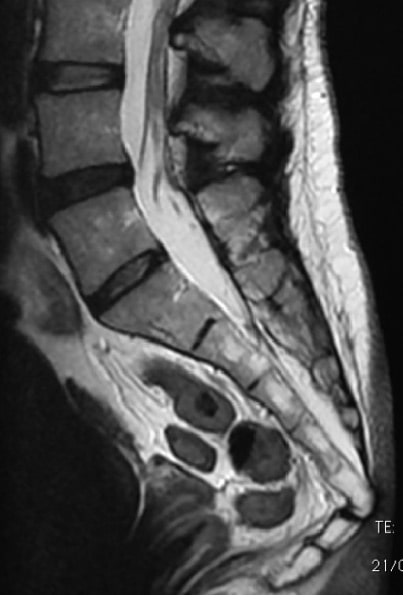

Trata-se da luxação cujo diagnóstico, mediante exames complementares, costuma ser o menos frequente. Isto porque, nas radiografias e nas ressonâncias magnéticas feitas na coluna completa ou, inclusive, na zona lombo-sacra, por conta de outros quadros ou suspeitas, não é possível visualizar o cóccix da vértebra S2 para baixo. Mesmo quando se realizam exames complementares que chegam até o final do cóccix, pode ser difícil detectar a separação mediante uma imagem radiológica, sendo necessário fazer uma tomografia computadorizada ou uma ressonância magnética.